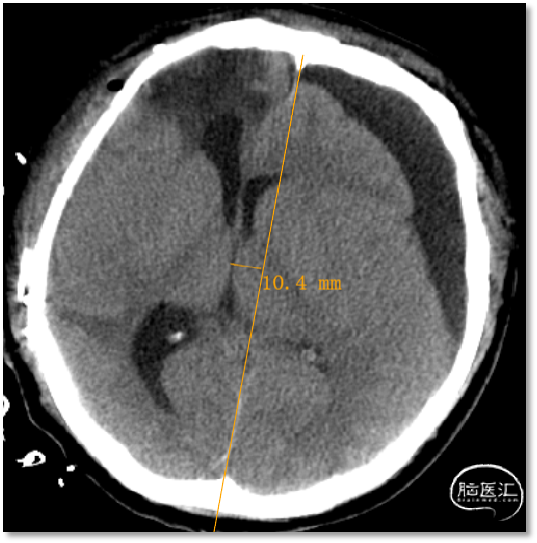

■ 检查:CT:颅骨缺损,左侧硬膜下积液,左侧脑室受压,中线右移;脑电:Synek分级-I级;SEP:N20电位存在。

术前

术后第二天

术后第七天

硬膜下积液明显减少,中线移位情况明显改善,患者出院